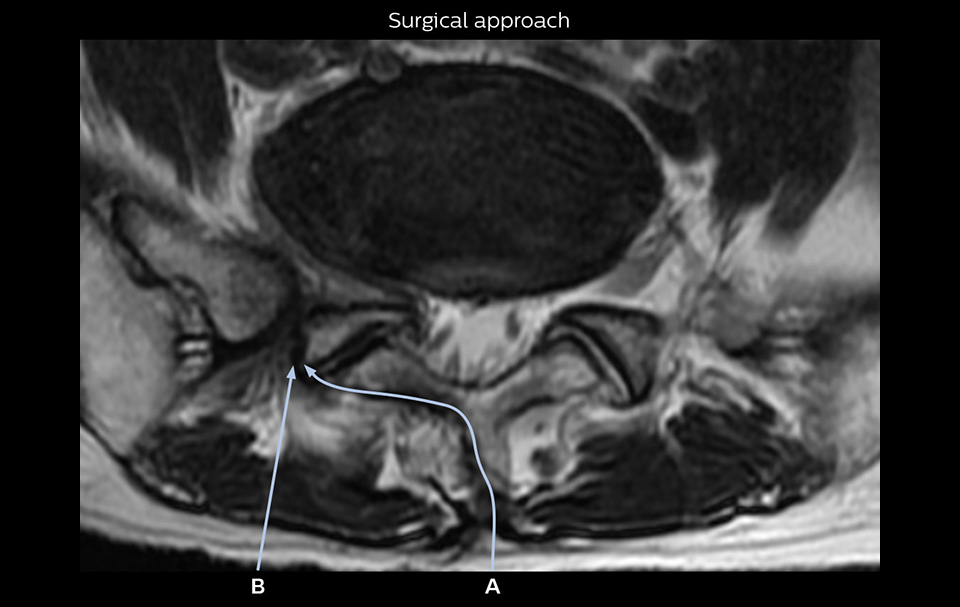

“Recently, the two surgical methods extreme and oblique lateral interbody fusion (XLIF and OLIF) have become mainstream for minimally invasive treatment of lumbar spinal canal stenosis and intervertebral foramen stenosis. With these surgical techniques, the spine is approached from the flank, and prior knowledge of the exact anatomy of the lumbosacral plexus would be extremely helpful. To that end, high slice resolution (less than 1 mm acquisition) that enables sharper sagittal MPR images will be needed.”

“For both brachial and lumbar plexus, we are currently using a 230 mm FOV and voxels of about 1 x 1 x 2 mm acquired (1 x 1 x 1 mm reconstructed). This provides us a good representation of the nerves, even though this FOV is relatively small. Regarding the inplane resolution, we hope to be able to bring that down to 0.7 mm, similar to our typical 2D multislice T2W images,” says Tanji.